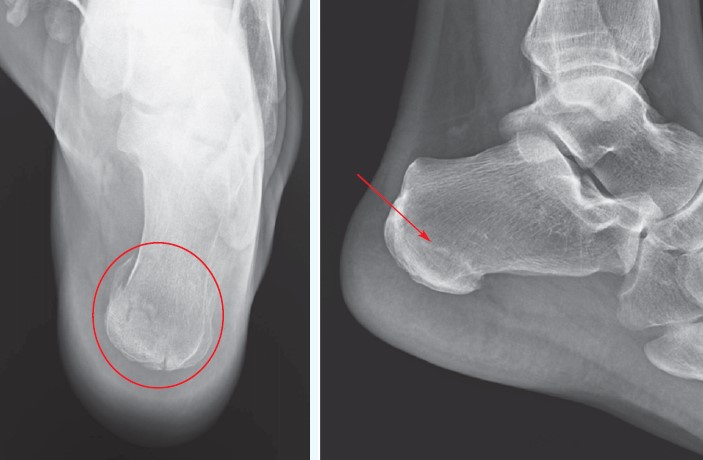

Calcaneal Stress Fracture How to differentiate stress fractures

Calcaneal fracture Radiology Reference Article Radiopaedia

What is a Calcaneal Stress Fracture How to Recover Upswing Health clearance, Calcaneus Fracture Broken Heel Bone Orthopaedic Trauma clearance, Calcaneal Fracture Broken Heel Bone Plantar Fasciitis clearance, Calcaneus Fracture Symptoms Treatment by a Foot Specialist clearance, Calcaneus Fracture Broken Heel Bone Orthopaedic Trauma clearance, Calcaneal fracture Wikipedia clearance, Calcaneal Fracture Treatment Exercises FAQs Case clearance, Calcaneus Fracture Broken Heel Bone Orthopaedic Trauma clearance, Calcaneus Heel Bone Fractures OrthoInfo AAOS clearance, Intraarticular Calcaneal Florida Orthopaedic Institute clearance, Calcaneal Stress Fracture Symptoms Causes Treatment clearance, Fracture of the Heel Bone Calcaneus Southeast Podiatry clearance, Heal Bone Fractures Calcaneal Fractures clearance, When There Is A Traumatic Fracture Of The Inferior Heel Spur clearance, Did I Break My Heel Bone Dr. Elton clearance, Calcaneus Heel Bone Fractures OrthoInfo AAOS clearance, Did I Bruise Or Fracture My Heel The Orthopaedic Foot Ankle clearance, Fractures of the Heel Bone Injuries and Poisoning MSD Manual clearance, Calcaneus Fracture Broken Heel Bone Campbell Clinic Orthopaedics clearance, Plantar Fasciitis vs Stress Fracture Angleton ER clearance, Can a Stress Fracture Cause Heel Pain The Foot Care Group Board clearance, Stress Fracture of the Calcaneus Symptoms Causes BEST Treatment clearance, Fractures of the Heel UConn Musculoskeletal Institute clearance, Plantar Fasciitis and Bone Spurs OrthoInfo AAOS clearance, Clinical Practice Guidelines Calcaneus Fractures Emergency clearance, Calcaneus Fracture Broken Heel Bone Campbell Clinic Orthopaedics clearance, Fractures Breaks and Plantar Fasciitis Heel That Pain clearance, Calcaneus Heel Bone Fractures Heel Pain Treatment clearance, A Calcaneal Stress Fracture Means a Broken Heel Bone clearance, Calcaneal Stress Fracture How to differentiate stress fractures clearance, Calcaneus Fracture Broken Heel Bone Orthopaedic Trauma clearance, Heel Bone Fracture Treatment Options OrthoIndy Blog clearance, Calcaneal fracture Radiology Reference Article Radiopaedia clearance, Calcaneal Fracture Shattered Heel A Success Story clearance, 35 Year Old With Heel Pain After a Fall Page 2 of 2 Journal of clearance, Calcaneal Squeeze Test Heel Squeeze clearance, Heel Pain Causes Treatment and When to See a Doctor clearance, Plantar Fasciitis vs. Stress Fractures Heel That Pain clearance, Calcaneal stress fractures Identification and treatment clearance, Heel Pain Treatment Lincoln NE Heel Fracture Treatment Omaha clearance, Heel Pain Podiatrist in Old Bridge and Sayreville NJ Jason Grossman DPM clearance, Pin by tilldeathwedoart on Dreamy Fracture Bone fracture clearance, Film ankle X ray radiograph showing heel bone fracture Calcaneus clearance, Calcaneus stress fracture Signs symptoms and treatment options clearance, Heel Fat Pad Syndrome Symptoms Causes Treatment clearance, Calcaneal Fracture Allied Medical Training clearance, Broken Heel Bone Fracture Causes Symptoms Best Home Treatment clearance, Posterior heel pain Chelsea and Westminster Hospital NHS clearance, Calcaneus Stress Fracture Dr Geier clearance, Plantar Fasciitis and Bone Spurs OrthoInfo AAOS clearance.

What is a Calcaneal Stress Fracture How to Recover Upswing Health clearance, Calcaneus Fracture Broken Heel Bone Orthopaedic Trauma clearance, Calcaneal Fracture Broken Heel Bone Plantar Fasciitis clearance, Calcaneus Fracture Symptoms Treatment by a Foot Specialist clearance, Calcaneus Fracture Broken Heel Bone Orthopaedic Trauma clearance, Calcaneal fracture Wikipedia clearance, Calcaneal Fracture Treatment Exercises FAQs Case clearance, Calcaneus Fracture Broken Heel Bone Orthopaedic Trauma clearance, Calcaneus Heel Bone Fractures OrthoInfo AAOS clearance, Intraarticular Calcaneal Florida Orthopaedic Institute clearance, Calcaneal Stress Fracture Symptoms Causes Treatment clearance, Fracture of the Heel Bone Calcaneus Southeast Podiatry clearance, Heal Bone Fractures Calcaneal Fractures clearance, When There Is A Traumatic Fracture Of The Inferior Heel Spur clearance, Did I Break My Heel Bone Dr. Elton clearance, Calcaneus Heel Bone Fractures OrthoInfo AAOS clearance, Did I Bruise Or Fracture My Heel The Orthopaedic Foot Ankle clearance, Fractures of the Heel Bone Injuries and Poisoning MSD Manual clearance, Calcaneus Fracture Broken Heel Bone Campbell Clinic Orthopaedics clearance, Plantar Fasciitis vs Stress Fracture Angleton ER clearance, Can a Stress Fracture Cause Heel Pain The Foot Care Group Board clearance, Stress Fracture of the Calcaneus Symptoms Causes BEST Treatment clearance, Fractures of the Heel UConn Musculoskeletal Institute clearance, Plantar Fasciitis and Bone Spurs OrthoInfo AAOS clearance, Clinical Practice Guidelines Calcaneus Fractures Emergency clearance, Calcaneus Fracture Broken Heel Bone Campbell Clinic Orthopaedics clearance, Fractures Breaks and Plantar Fasciitis Heel That Pain clearance, Calcaneus Heel Bone Fractures Heel Pain Treatment clearance, A Calcaneal Stress Fracture Means a Broken Heel Bone clearance, Calcaneal Stress Fracture How to differentiate stress fractures clearance, Calcaneus Fracture Broken Heel Bone Orthopaedic Trauma clearance, Heel Bone Fracture Treatment Options OrthoIndy Blog clearance, Calcaneal fracture Radiology Reference Article Radiopaedia clearance, Calcaneal Fracture Shattered Heel A Success Story clearance, 35 Year Old With Heel Pain After a Fall Page 2 of 2 Journal of clearance, Calcaneal Squeeze Test Heel Squeeze clearance, Heel Pain Causes Treatment and When to See a Doctor clearance, Plantar Fasciitis vs. Stress Fractures Heel That Pain clearance, Calcaneal stress fractures Identification and treatment clearance, Heel Pain Treatment Lincoln NE Heel Fracture Treatment Omaha clearance, Heel Pain Podiatrist in Old Bridge and Sayreville NJ Jason Grossman DPM clearance, Pin by tilldeathwedoart on Dreamy Fracture Bone fracture clearance, Film ankle X ray radiograph showing heel bone fracture Calcaneus clearance, Calcaneus stress fracture Signs symptoms and treatment options clearance, Heel Fat Pad Syndrome Symptoms Causes Treatment clearance, Calcaneal Fracture Allied Medical Training clearance, Broken Heel Bone Fracture Causes Symptoms Best Home Treatment clearance, Posterior heel pain Chelsea and Westminster Hospital NHS clearance, Calcaneus Stress Fracture Dr Geier clearance, Plantar Fasciitis and Bone Spurs OrthoInfo AAOS clearance.